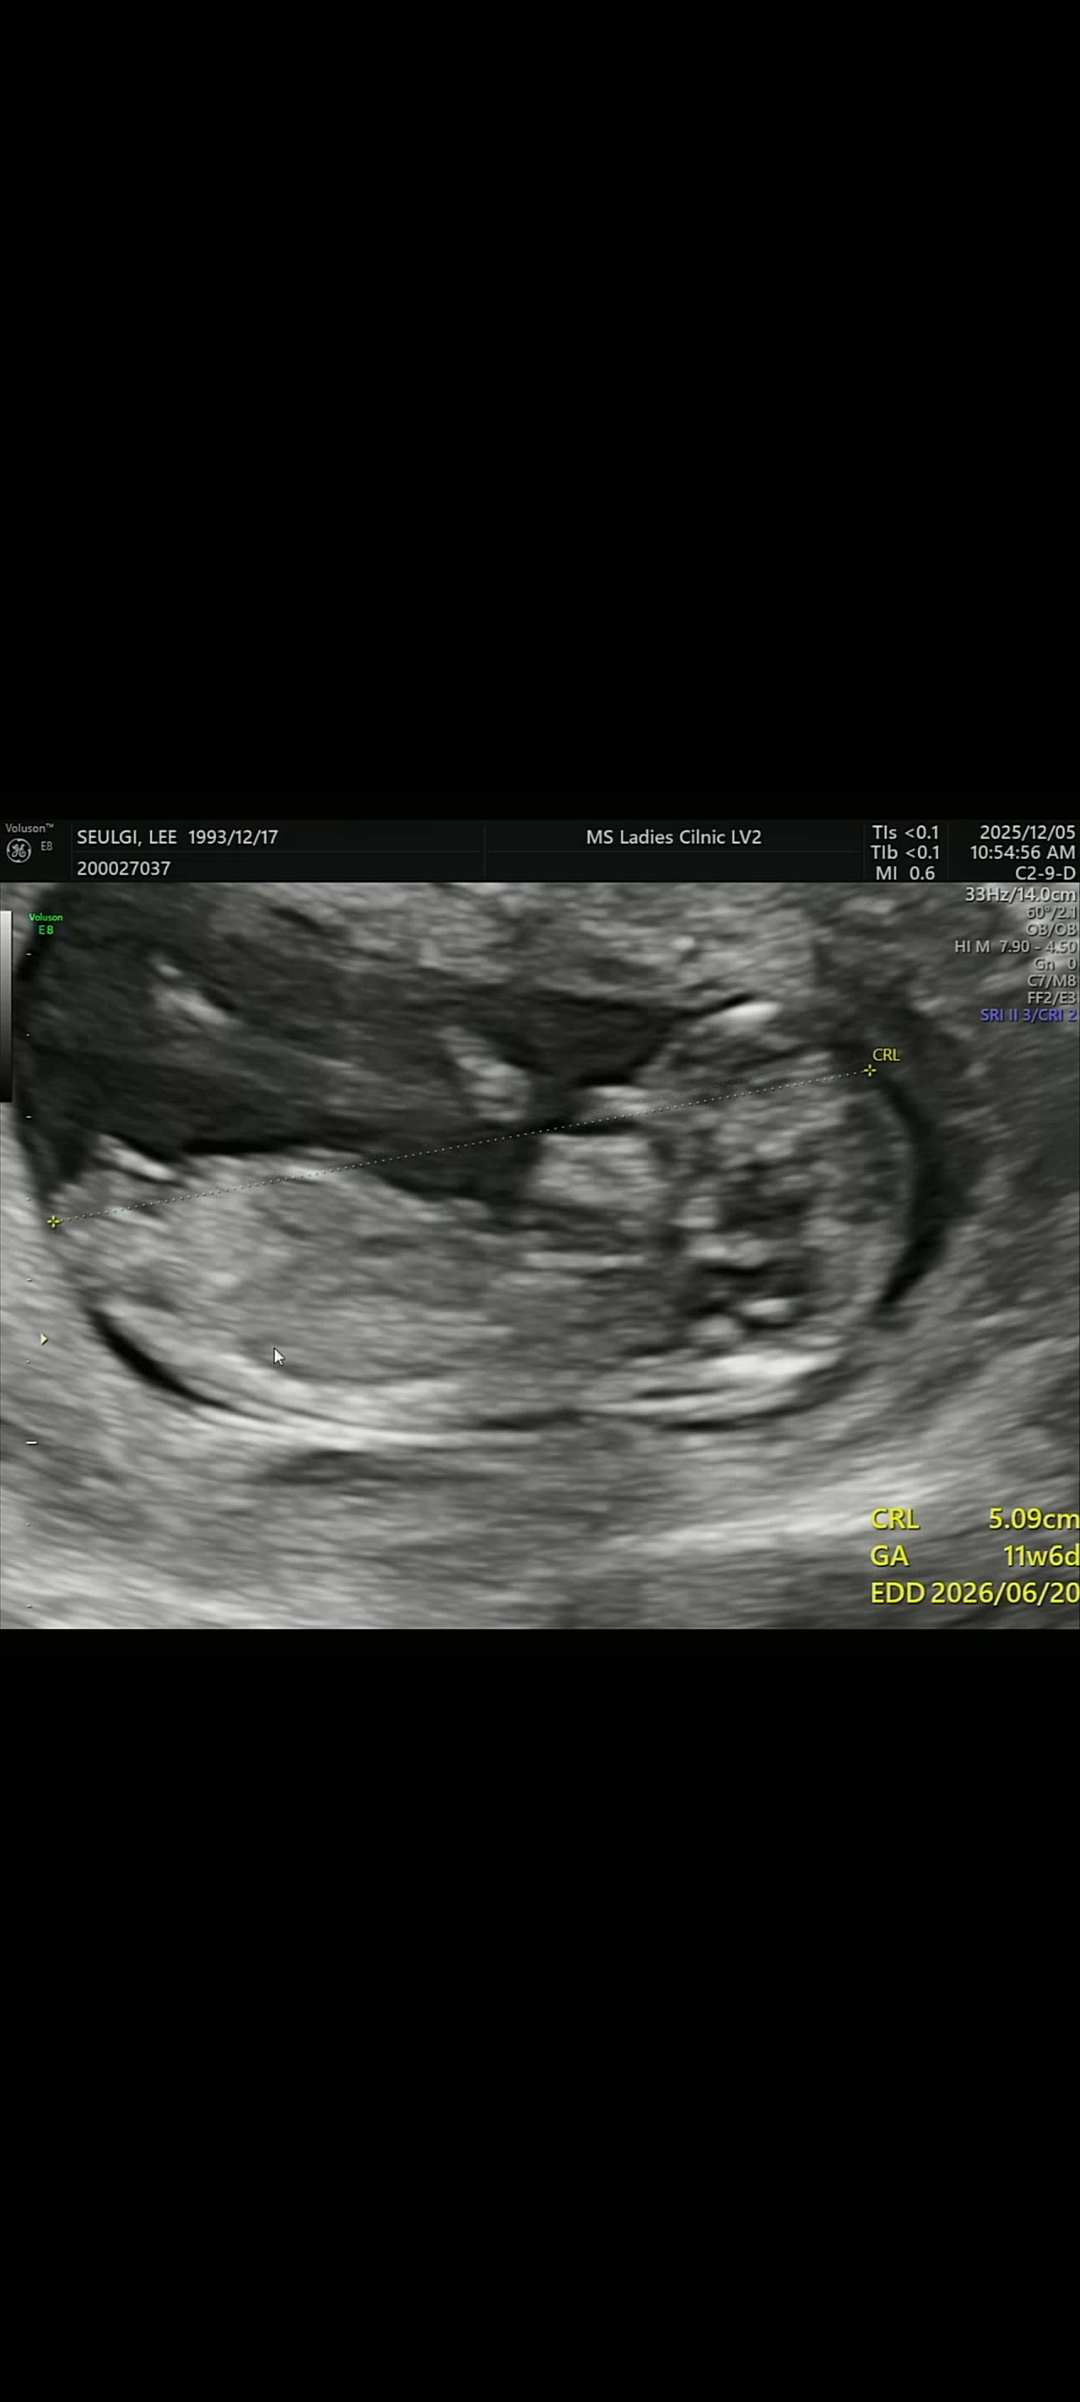

11주6일 사진이에요~!